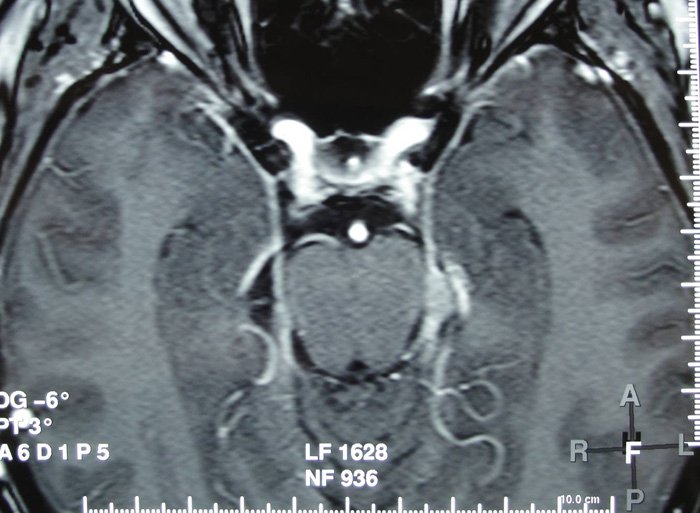

Devant ce tableau clinique vous demandez une IRM médullaire.

- la mise en évidence à l’IRM d’un hypersignal en T2 au niveau des cordons postérieurs, touchant plusieurs myelomères (plutôt localisé à 1 ou 2 niveaux en cas de SEP)